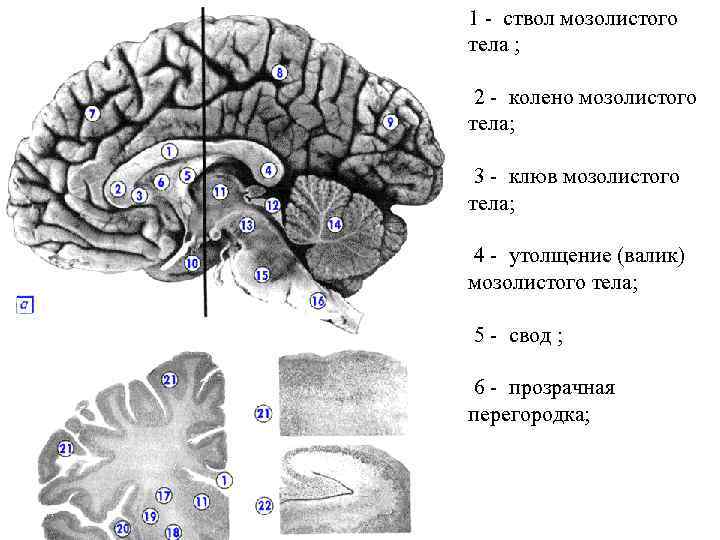

Необычные объекты: Переднее продырявленное вещество

Раздел: Альбом открытий